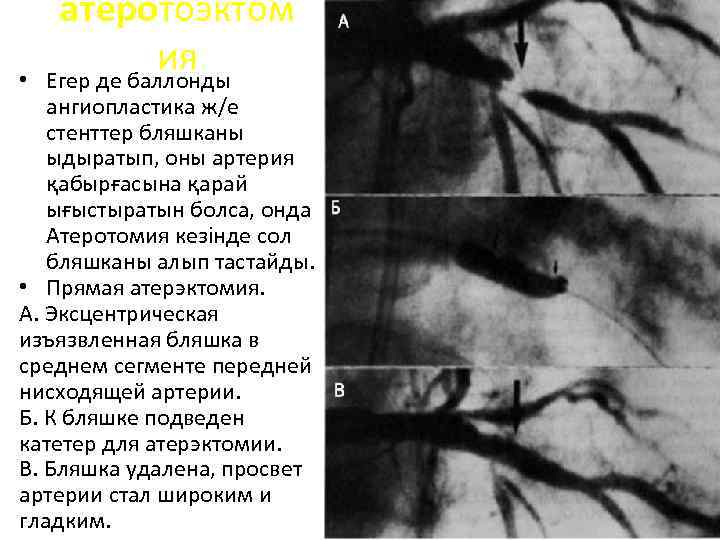

• атеротоэктом ия Егер де баллонды ангиопластика ж/е стенттер бляшканы ыдыратып, оны артерия қабырғасына қарай ығыстыратын болса, онда Атеротомия кезінде сол бляшканы алып тастайды. • Прямая атерэктомия. А. Эксцентрическая изъязвленная бляшка в среднем сегменте передней нисходящей артерии. Б. К бляшке подведен катетер для атерэктомии. В. Бляшка удалена, просвет артерии стал широким и гладким.

• атеротоэктом ия Егер де баллонды ангиопластика ж/е стенттер бляшканы ыдыратып, оны артерия қабырғасына қарай ығыстыратын болса, онда Атеротомия кезінде сол бляшканы алып тастайды. • Прямая атерэктомия. А. Эксцентрическая изъязвленная бляшка в среднем сегменте передней нисходящей артерии. Б. К бляшке подведен катетер для атерэктомии. В. Бляшка удалена, просвет артерии стал широким и гладким.